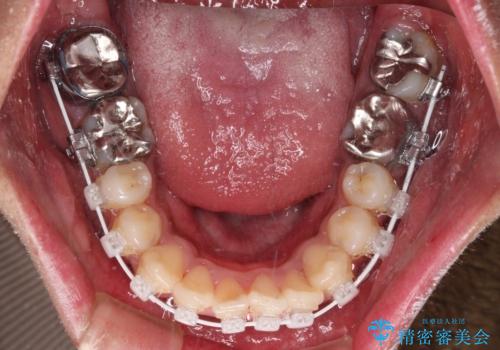

自己管理が煩わしいとのことで、表側のワイヤー装置にて治療を進めて行くこととしました。

舌の突出癖により開咬となっていたため、突出癖改善のためのトレーニングをしっかりと行っていただき、予定の期間で無事に治療を終えることができました。